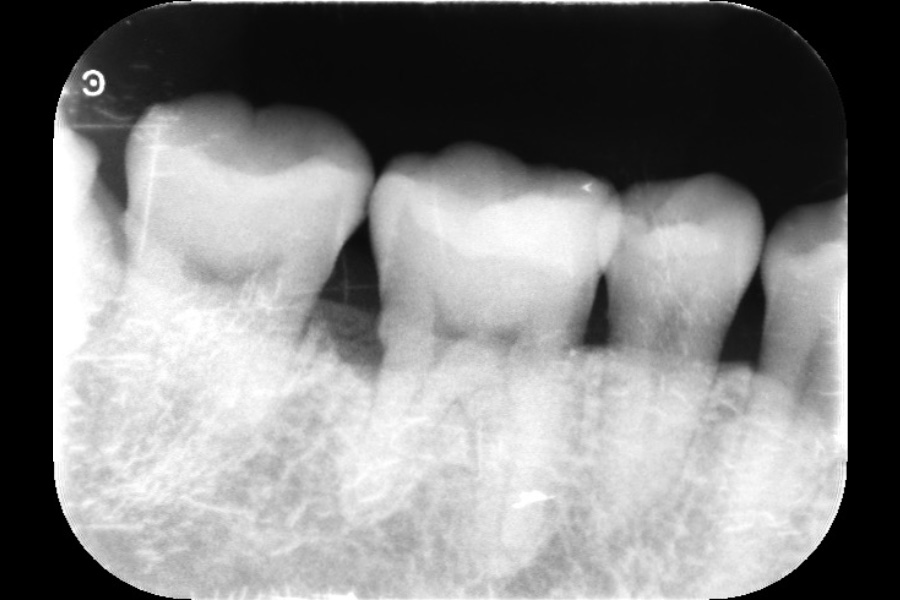

右下奥歯の歯ぐきから出血する

【歯周組織再生療法】

- 主訴

- 右下奥歯の歯ぐきから出血する

- 期間

- 再生療法から再評価まで6か月

- 費用

- ¥220,000(税込)

- 治療内容

- 右下4遠心に垂直性骨吸収が認められたためエムドゲインと骨補填材を用いて歯周組織再生療法を行った

- 治療に伴うリスク

- 歯肉退縮、知覚過敏